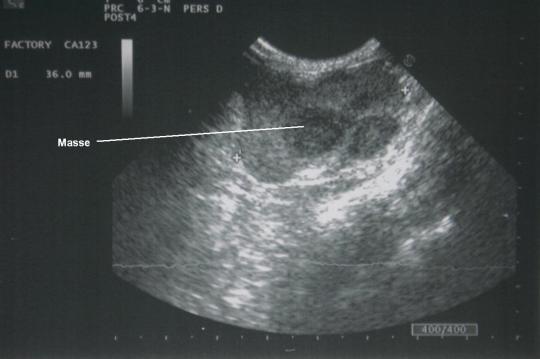

Die Kätzin wird vor der Narkoseeinleitung routinemässig untersucht. Dabei ist eine derbe, elastische, kugelige Masse von etwa 3 cm im oberen, linken Bereich der Bauchhöhle tastbar. Die restliche Untersuchung verläuft normal. Im Ultraschall ist der Knoten ebenfalls identifizierbar: Die Masse weist zwei unterschiedlich echodichte Regionen auf – eine hypoechogenes („dunkles“), gelapptes Zentrum und eine hyperechogene („helle“) Randzone. Die restliche Bauchhöhle scheint im Ultraschall unauffällig.